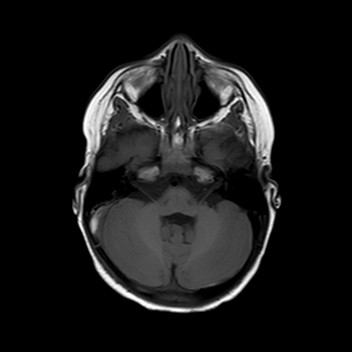

Esegue quindi una TAC che mostra una frattura

dell’osso occipitale con la presenza di un ematoma epidurale

di circa 9 mm adiacente al seno sigmoideo di destra.

La bambina inizia quindi terapia con enoxaparina alla dose di 1700 UI x 2/die con aggiunta di terapia antibiotica con ampicillina-sulbactam per profilassi. Nei giorni successivi Teresa è stata bene, l’instabilità è andata progressivamente scomparendo senza vomito o cefalea. I successivi controlli all’angio-RM e alla TAC hanno mostrato un rallentamento del flusso in seno sigmoideo destro con tumefazione e netta iperdensità dello stesso, che sono andati progressivamente scomparendo con solo una minima falda ematica residua al giorno della dimissione, dieci giorni dopo il trauma. La terapia è stata dimezzata e poi interrotta dopo tre settimane dall’avvio.

La presenza di atassia alla marcia con vomito è un segno tipico della trombosi del seno sigmoideo che, per quanto rara nel bambino dopo un trauma, va esclusa con una angio-RM, non essendo la TAC in grado di visualizzare chiaramente il flusso nei seni venosi, soprattutto se all’immagine si sovrappone la contestuale presenza di un ematoma. Inoltre la progressione dei sintomi neurologici indicava il trattamento del trombo con eparina, a differenza dei casi asintomatici dove è indicata la semplice reidratazione per evitarne la progressione e lo sviluppo di ipertensione endocranica.